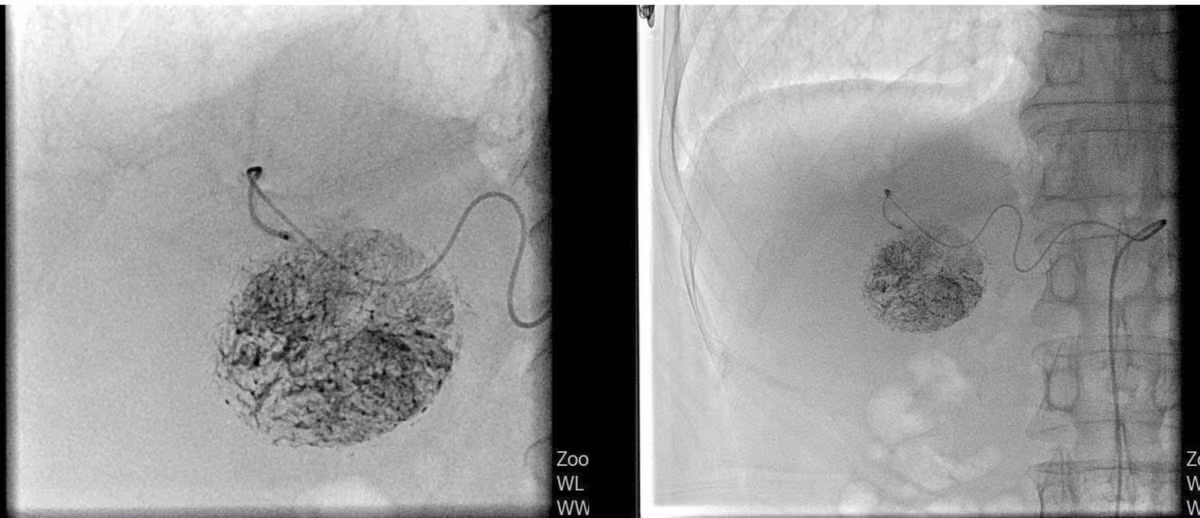

Hình ảnh khối u chụp cắt lớp vi tính trước can thiệp - Ảnh BVCC

Trong quá trình thăm khám, bác sĩ phát hiện khối u gan hạ phân thùy IV-V, kích thước khoảng 5x6 cm, giàu mạch máu – được chẩn đoán là ung thư biểu mô tế bào gan.